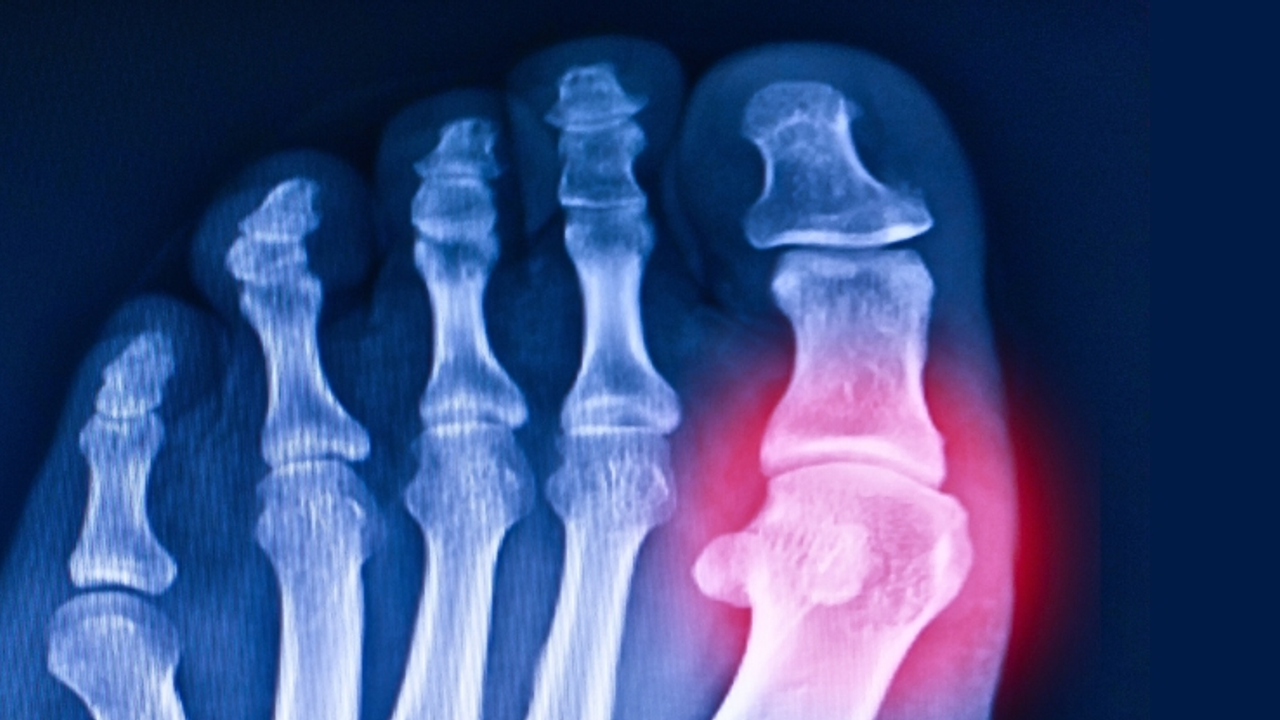

Gut, binlerce yıldır bilinen acılı bir hastalık. Kanda ürik asit fazlalığı nedeniyle eklemlerde ve böbreklerde kristal oluşuyor. Bu durum yalnızca gutu değil, böbrek hastalıklarını ve karaciğer sorunlarını da tetikliyor.